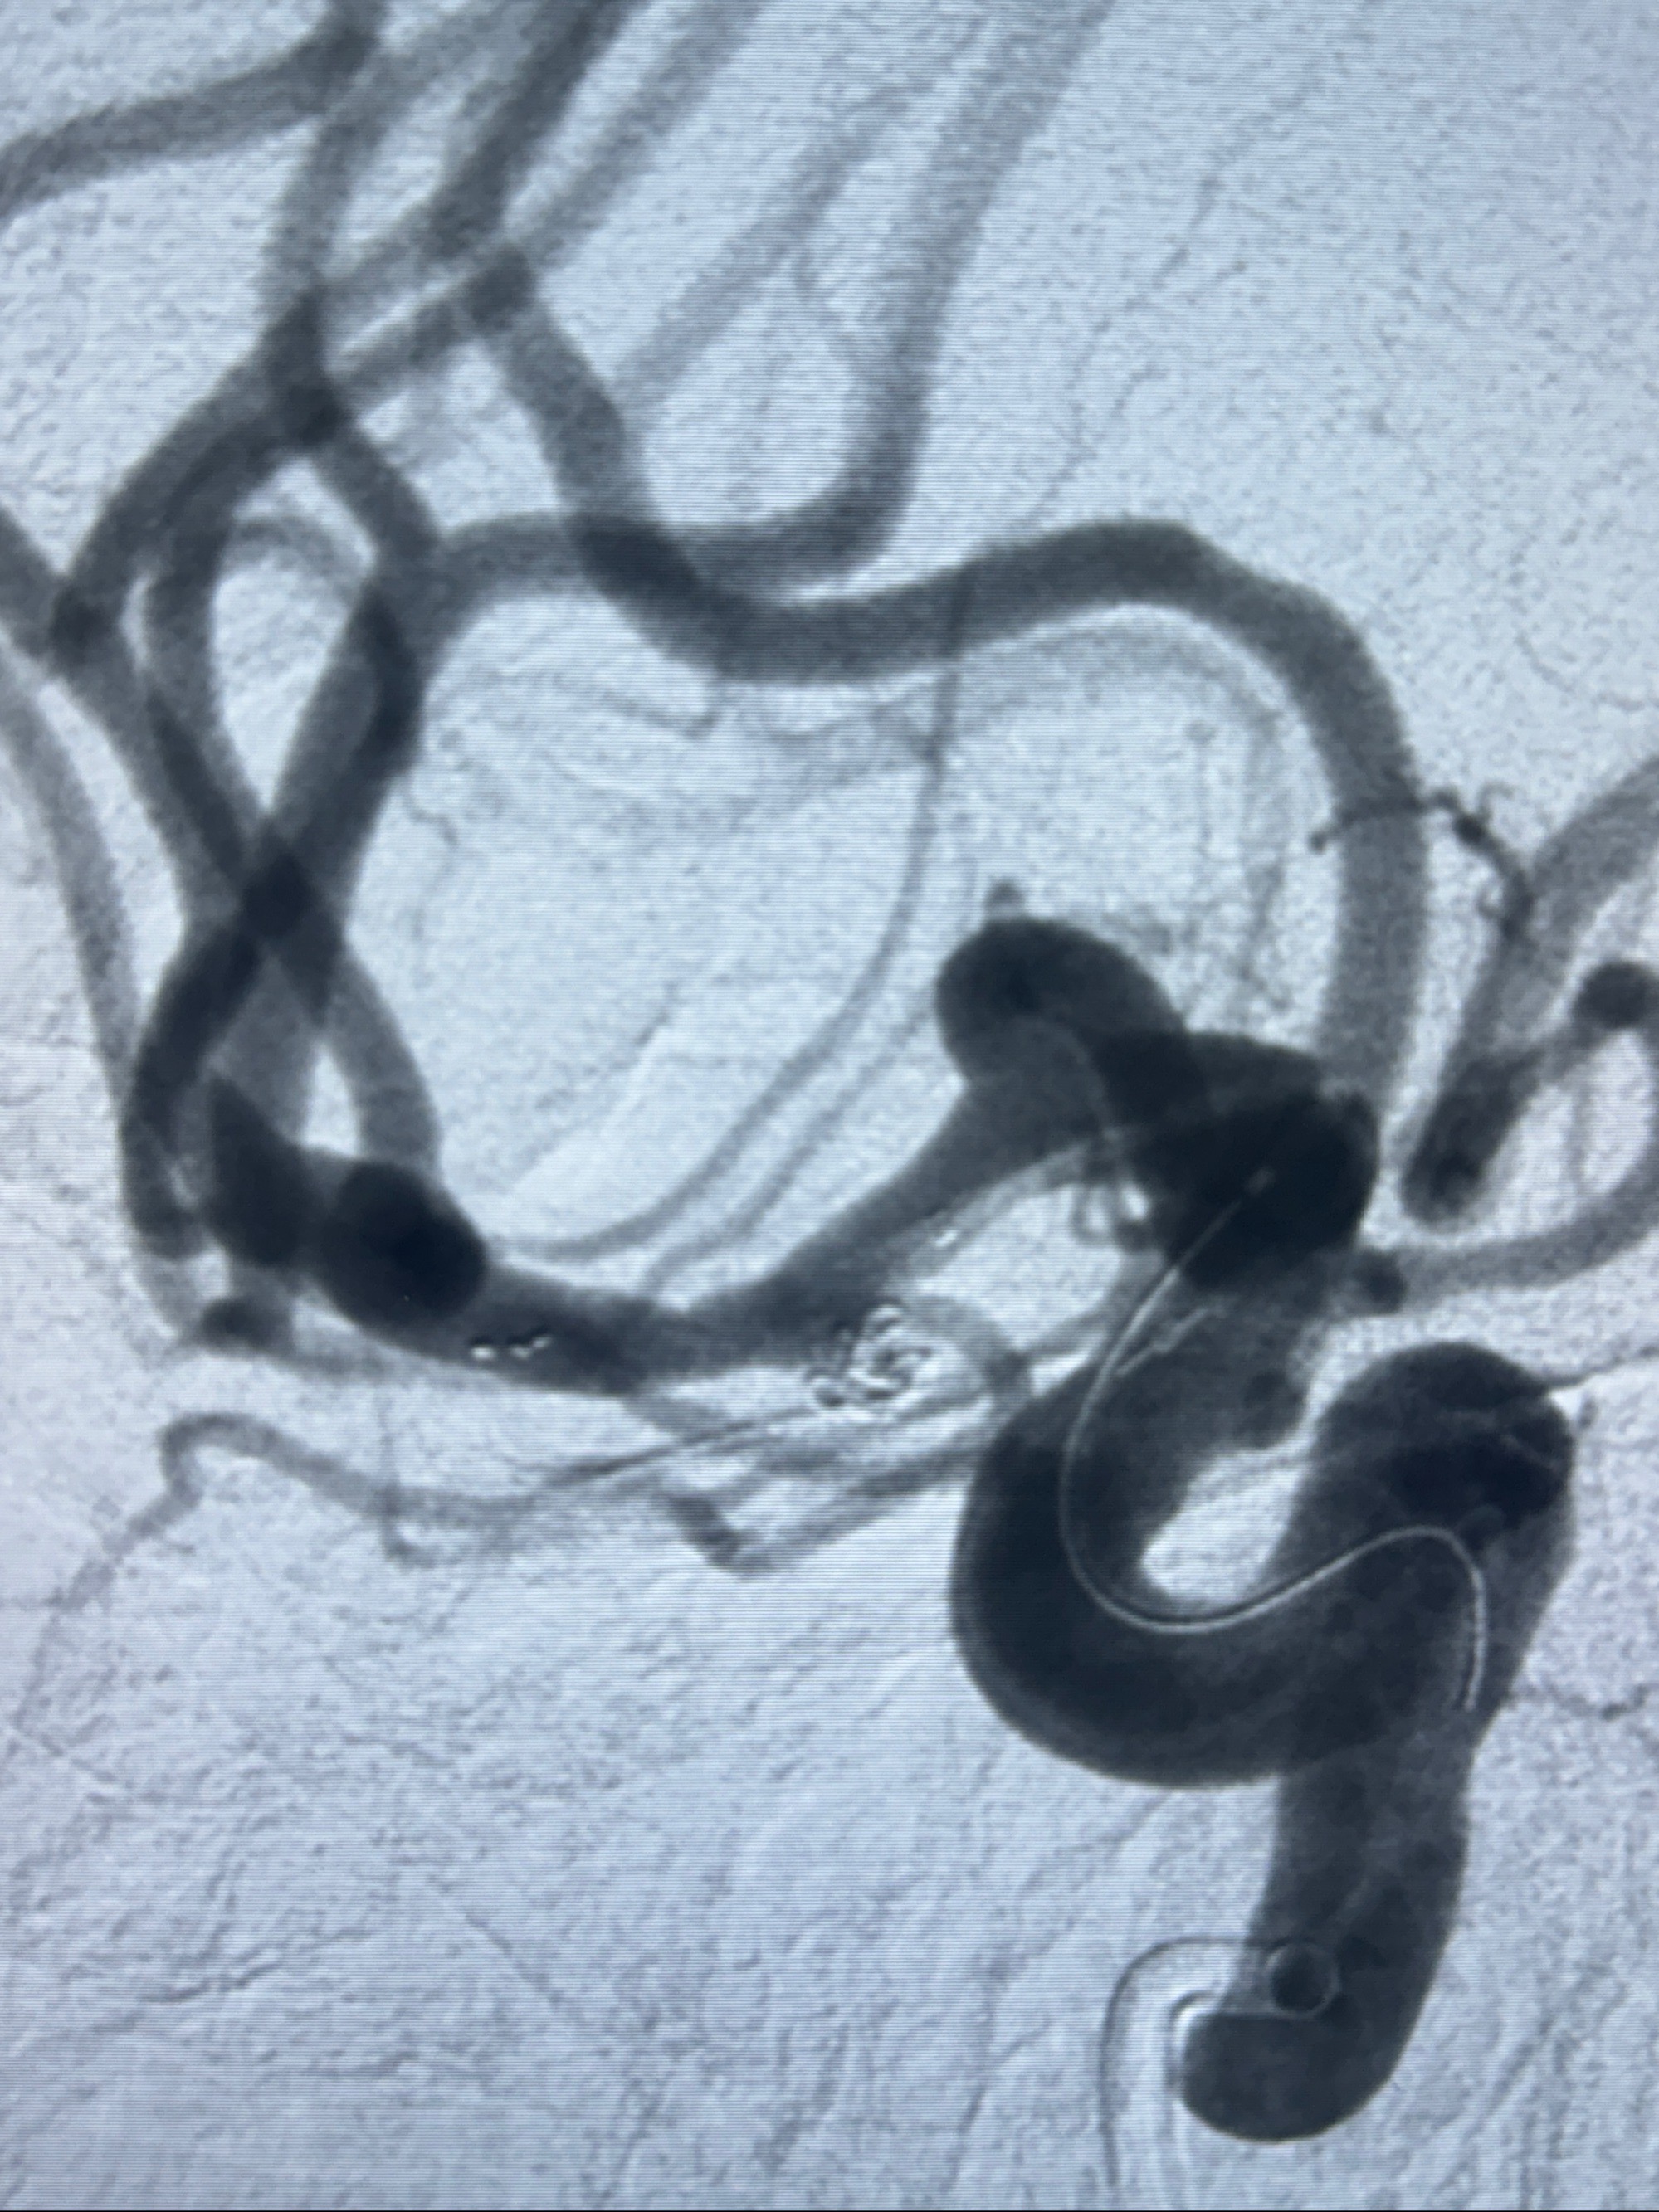

2023-11-24DSA:右侧大脑中动脉下干起始部动脉瘤,约2.3*2.5mm,形态规则

治疗策略:

- 随访?

- 夹闭?

- 单弹簧圈填塞?

- 支架辅助治疗?

2023-12-04全麻下行支架辅助治疗

S-AB4-20mm